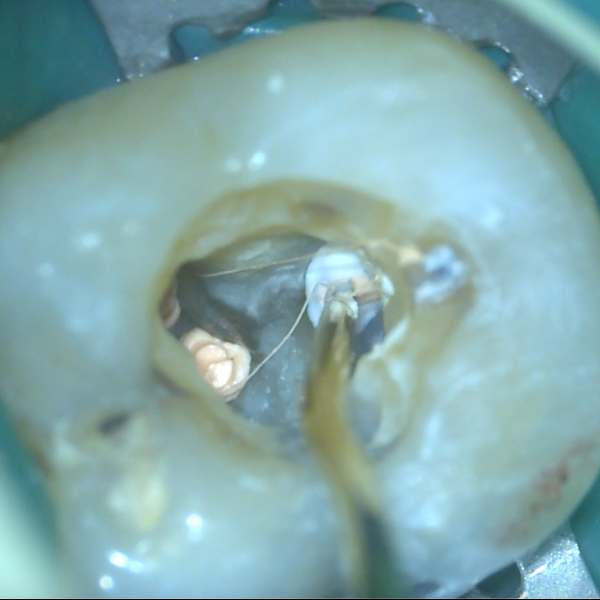

Kalcium silikátové materiály si od svého uvedení na trh získaly pověst vhodných materiálů pro zaplnění širokých kořenových kanálků nebo jiných situací v rámci endodontického ošetření, kde je materiál v kontaktu s nadměrnou vlhkostí.

Zároveň si však získaly pověst materiálů s obtížnou manipulací, což vedlo výrobce k vývoji předmíchaných kalcium silikátových sealerů. Tyto sealery nabízejí jednoduchou manipulaci, zejména při technice hydraulické kondenzace, kdy se zavádí pouze hlavní gutaperčový čep.

V určitých případech může být výhodná pístová technika. V rámci přednášky se dozvíte základní informace o kalcium silikátových materiálech – kdy je vhodné je využít, o kalcium silikátových sealerech – jaké existují, a také praktické informace o pístové technice – jak a kdy ji provést, jak si zjednodušit život a jak se vyhnout komplikacím.

Shrnutí kalcium silikátových sealerů a potřebného vybavení pro rychlé a efektivní zaplnění kořenových kanálků pomocí pístové techniky: